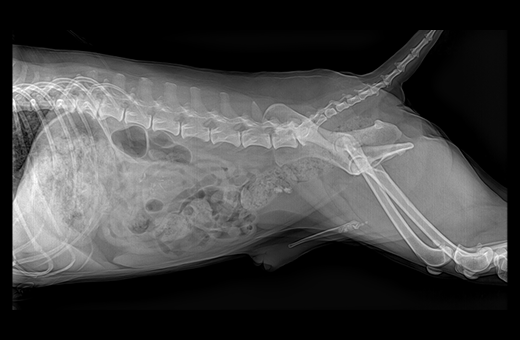

음경 요도(penile urethra)에 걸린 결석 1

· 방사선 검사

배뇨 곤란으로 내원하게 되면 일반적으로 방사선 검사가 가장 우선시 되게 됩니다.

방사선 검사에서는 결석이 어느 위치에 분포되어 있는지, 폐색으로 인한 방광 확장 정도가 어느 정도인지 등을 우선적으로 평가합니다.